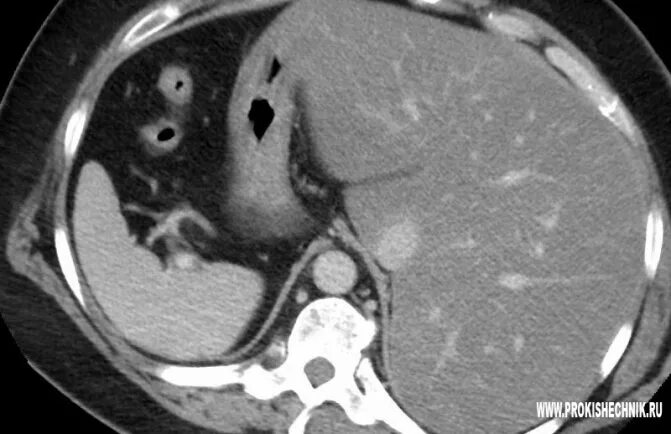

Цирроз на кт